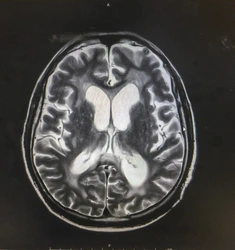

Είναι σημαντικό να τονισθεί ότι η αστάθεια, η δυσκολία στη βάδιση, τα προβλήματα μνήμης ή η ακράτεια μπορεί να οφείλονται σε μια συχνή αλλά όχι τόσο γνωστή πάθηση: τον Υδροκέφαλο Φυσιολογικής Πίεσης, στον οποίο υπάρχει συσσώρευση υγρού (εγκεφαλονωτιαίο υγρό) στις κοιλότητες (κοιλίες) του εγκεφάλου με αποτέλεσμα να μεγαλώνουν σε μέγεθος και να πιέζουν τον εγκέφαλο. Είναι χαρακτηριστικό ότι οι ασθενείς αυτοί αναφέρουν ότι δυσκολεύονται να περπατήσουν και νοιώθουν ότι κολλούν τα πόδια τους στο έδαφος, κάτι που ιατρικώς περιγράφεται ως «μαγνητικό βάδισμα».

Η θεραπεία των ασθενών με Υδροκέφαλο Φυσιολογικής Πίεσης περιλαμβάνει την τοποθέτηση βαλβίδας εγκεφάλου (κοιλιοπεριτοναικής βαλβίδα εγκεφάλου), που παροχετεύει το εγκεφαλονωτιαίο υγρό από τον εγκέφαλο στην κοιλία. Η βαλβίδα εγκεφάλου ρυθμίζει την ροή του εγκεφολονωτιαίου υγρού που δεν μπορεί να διαχειριστεί ο εγκέφαλος με αποτέλεσμα την μείωση του μεγέθους των κοιλιών του εγκεφάλου και την θεραπεία των ασθενών. Είναι χαρακτηριστικό ότι μια ασθενής μας με Υδροκέφαλο Φυσιολογικής Πίεσης περιέγραψε την ημέρα του χειρουργείου της για την τοποθέτηση βαλβίδας εγκεφάλου ως «Τα νέα της γενέθλια», γιατί η ζωή της βελτιώθηκε τόσο πολύ μετά την επέμβαση που ένοιωσε ότι ξαναγεννήθηκε!